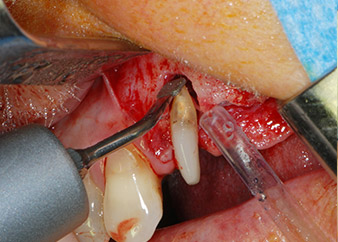

Sinus lift and implant placement

Prior to implant placement, infected tissue was removed from the alveolar bone in the implant site and around the abutment teeth with an insert originally designed for bone shaping and collecting bone chips (Piezomed, insert B5) (Figs. 6 and 7).

Implant beds were prepared at sites 25 and 26 with rotary instruments, used in a contra-angle handpiece with a 20 : 1 transmission ratio with an updated powerful implant motor (Implantmed, W&H) (Fig. 8).

The final preparation next to the sinus was again carried out with a piezoelectric instrument (Piezomed, insert S2).

Prior to implant placement, and following verification of an intact Schneiderian membrane (Fig. 9), the internal sinus floor was augmented at both implant sites by means of xenogeneic bone substitute material (Bio-Oss, Geistlich Biomaterials) (Fig. 10).